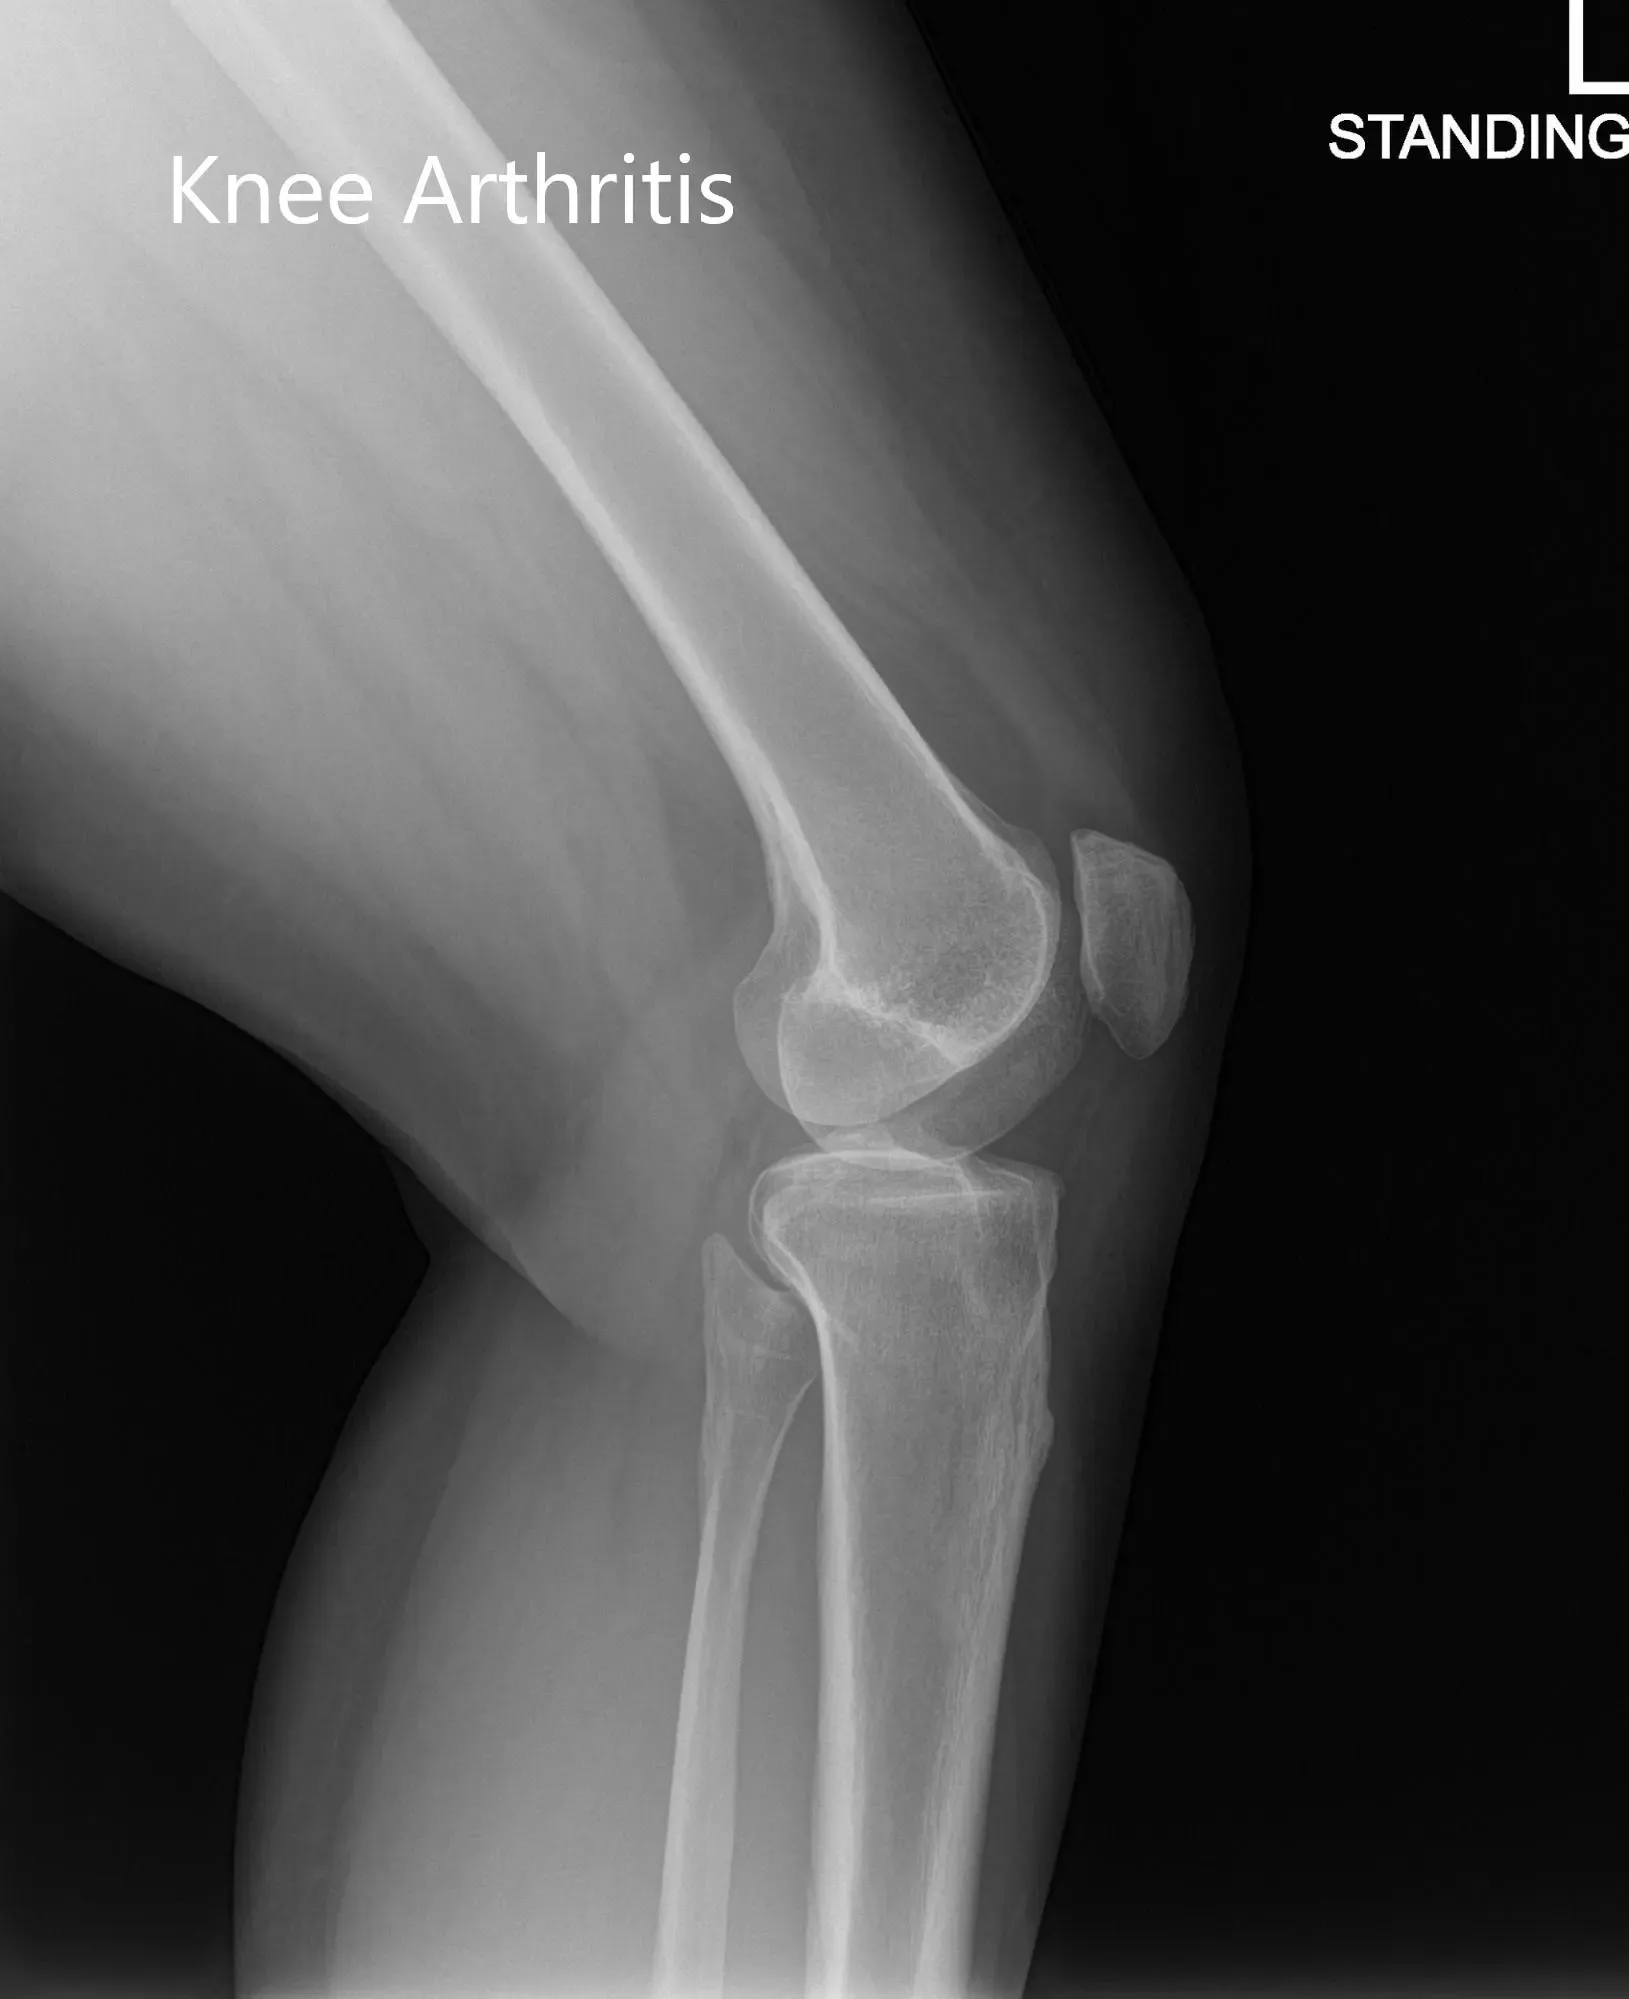

Su examen físico reveló sensibilidad en la línea articular medial con inflamación leve. La rodilla no mostró inestabilidad en las pruebas de esfuerzo anterior, posterior, valgo y varo. Las imágenes revelaron artritis postraumática en la rodilla izquierda. Le pusieron una inyección de cortisona en la rodilla con un excelente control del dolor. Posteriormente, el paciente fue seguido en 3 meses.

Radiografía preoperatoria de la rodilla izquierda que mostró imágenes AP y laterales

Se realizó una tomografía computarizada preoperatoria de la rodilla izquierda del paciente para evaluar su biomecánica y anatomía. Los datos se utilizaron después para obtener imágenes 3D de la rodilla del paciente, ayudando a construir implantes e instrumentos únicos específicos de cada paciente. El reemplazo personalizado de rodilla ofrece una cirugía que preserva los huesos. Los implantes únicos específicos para el paciente aseguran la restauración de la superficie articulada natural y la geometría de la rodilla.